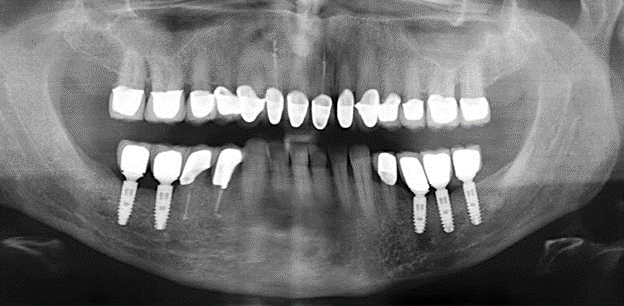

Fig. 4: Flexible probes with millimetre markings are recommended for the probing of dental implants (e.g. Colorvue Kit PCV11KIT6, Hu­Friedy). – Fig. 5a and b: A straight working tip (1P, W&H Dentalwerk Bürmoos GmbH) is a suitable instrument for use on all natural teeth. – Fig. 6: Curved working tips (3Pr/3Pl, W&H Dentalwerk Bürmoos GmbH) lend themselves to the processing of difficult-to-reach areas of the tooth and root surfaces (e.g. furcations). – Fig. 7: The tapered, hexagonal implant cleaning tip (1I, W&H Dentalwerk Bürmoos GmbH) permits atraumatic and efficient cleaning of the crown and abutment surfaces. – Fig. 8: Titanium and carbon curettes are suitable instruments for the manual cleaning of the implant surfaces.

Of course, working tips for the cleaning of implant surfaces are also indispensable for SPT in patients fitted with implants. The implant cleaning attachment on the system used here is characterised by its tapered, hexagonal design. This design allows light, atraumatic penetration of the peri-implant pocket and displays a good cleaning performance (Fig. 7).